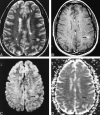

<sc>fig</sc> 1.

fig 1.

Examples of an NEL and an REL in a patient with MS. A–D, Axial T2-weighted image (4000/110/1) (A), contrast-enhanced T1-weighted image (500/20/1) (B), isotropic diffusion-weighted image (4000/125/1) (C), and trace ADC map (D) show a T1-weighted NEL (arrow) and a T1-weighted REL (arrowhead). Both lesions show increased diffusion on the trace ADC map.